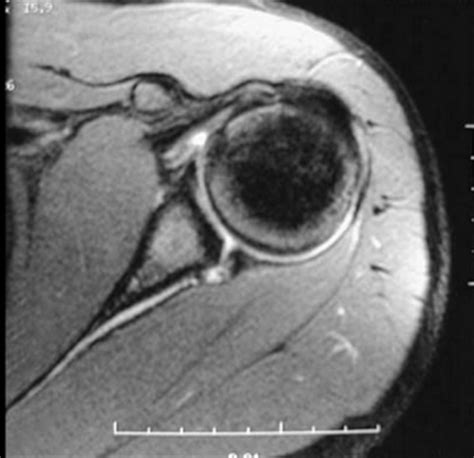

An MRI is a non-invasive imaging technique that uses magnetic fields and radio waves to produce detailed images of the body’s internal structures. For diagnosing a Slap Tear MRI, the scan provides high-resolution images of the shoulder joint, allowing radiologists to identify tears in the labrum and other soft tissue injuries.

During a Slap Tear MRI, the patient lies on a table that slides into a cylindrical machine. The machine emits magnetic fields and radio waves, which are detected by a receiver coil placed around the shoulder. The data collected is then processed by a computer to generate detailed images of the shoulder joint.

Slap Tear MRI scans are particularly useful for diagnosing SLAP tears because they provide clear images of the labrum and surrounding structures. However, interpreting the results requires expertise, as SLAP tears can be subtle and easily missed.

Interpreting the results of a Slap Tear MRI involves a thorough examination of the images by a radiologist. Key findings that indicate a SLAP tear include:

• Abnormal signal intensity within the labrum, suggesting a tear.

• Displacement or detachment of the labrum from the glenoid.

• Fluid or contrast agent extending into the tear, highlighting the extent of the injury.

• Associated injuries, such as rotator cuff tears or biceps tendon pathology.